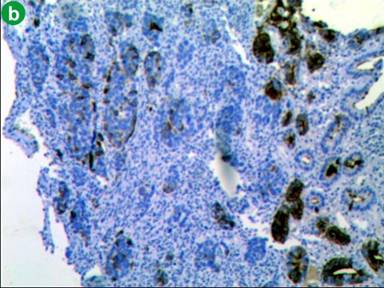

Patient underwent surgery, where a large mass of size 3 cm was found in the periampullary region with absence of body and tail of the pancreas confirming the diagnosis of agenesis of dorsal pancreas. A total pancreatectomy, duodenectomy, Roux-en-Y gastrojejunostomy, hepaticojejunostomy, and cholecystectomy were performed. On gross examination, a large ulceroinfiltrative lesion (3.0×2.5×2.0 cm) involving mostly periampullary region was found which was firm in consistency, pale greyish white in appearance with ill defined edges appearing to invade almost full thickness of the duodenal wall extending onto subserosa (Figure 3). Histopathological examination revealed invasive poorly differentiated adenocarcinoma with diffuse deep infiltration involving almost full thickness of the duodenal wall and invading subserosa (Figure 4a). Immunohistochemistry was done and the tumor cells were positive for immunohistochemical markers CA 19-9 (Figure 4b), cytokeratin-7, KI-67 (Figure 4c) and negative for CEA, cytokeratin-20. No lymph node metastasis was found.

Figure 4. a. Histopathological image of periampullary lesion (low power view) showing diffuse infiltration of tumor cells up to serosa off duodenum. b. Immunohistochemical staining of poorly differentiated tumor showing positive for tumor marker CA-19-9 and KI-67. c. Immunohistochemical staining of poorly differentiated tumor showing positivity for proliferative marker Ki-67. |

Our patient had periampullary carcinoma with agenesis of dorsal pancreas. Periampullary carcinoma is a tumor arising in the vicinity of the ampulla of Vater [17]. They can originate from the pancreas, duodenum and distal common bile duct [18]. These tumors are classified on the basis of their tissue of origin; they are different from the classical adenocarcinoma of the pancreas and they may be either benign or malignant tumors. Pathological examination of these tumors showed that 60% of are of pancreatic origin, 20% from ampulla of Vater, 20% from common bile duct and rest 10% arise from duodenum [18]. In literature around 9 cases pancreatic cancer have been reported in association with agenesis of dorsal pancreas. Among these pancreatic ductal adenocarcinoma was the most frequent, being reported in 5 patients, solid papillary tumor in 2 patients, IPMN with well differentiated, invasive mucinous adenocarcinoma in 1 patient and 1 patient with periampullary carcinoma [11, 19-23]. Only one case of periampullary carcinoma was reported by A Kapoor et al. [23] from India and ours is the second case. Our case had poorly differentiated adenocarcinoma and we did immunohistochemistry. Immunohistochemistry showed, tumor cells were positive for markers CA 19-9, KI-67, cytokeratin-7 (Figure 4b and 4c) and negative for intestinal markers like cytokeratin-20 and CEA (carcinoembryonic antigen) suggestive of pancreatico-biliary type of poorly differentiated adenocarcinoma. Pancreatico-biliary tumors follow a more aggressive course similar to that of pancreatic adenocarcinoma with worse prognosis. Our patient underwent total pancreatectomy and post operatively she developed insulin dependent diabetes mellitus.